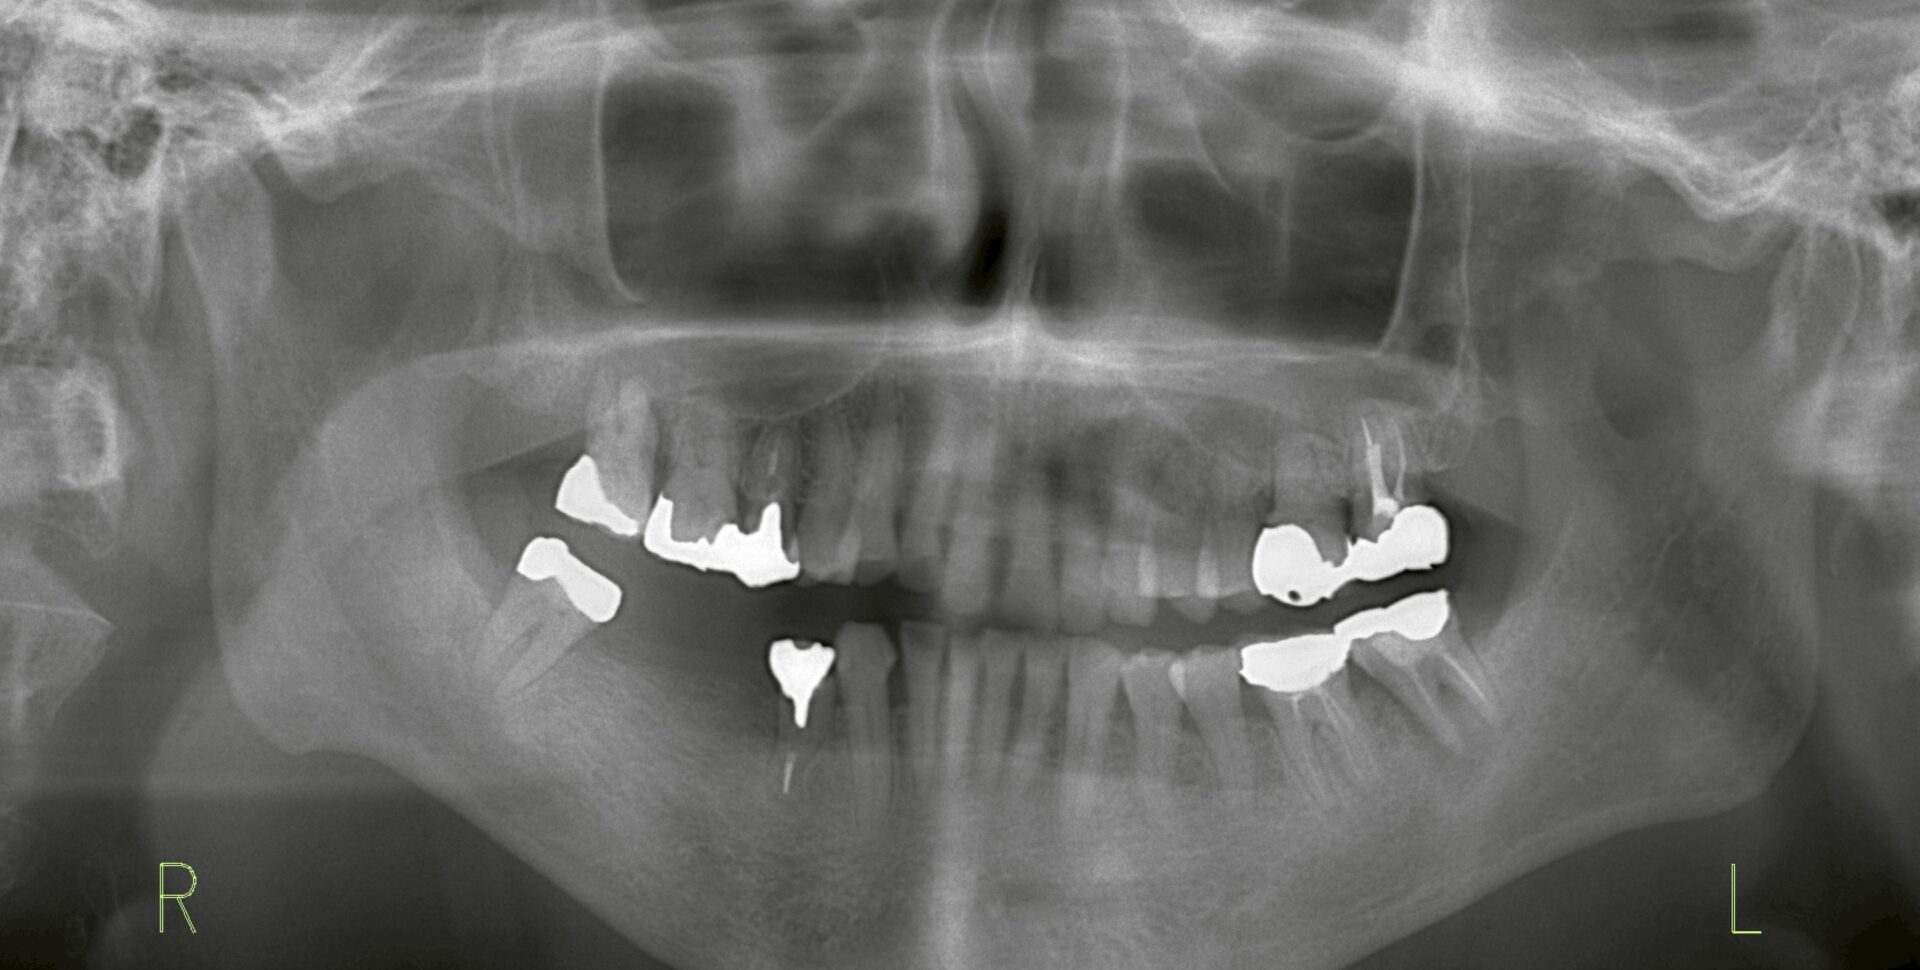

本来であれば、欠損している歯の位置(5番)と抜歯予定の位置(7番)に2本インプラントを埋入し、3本分のブリッジを計画するのが理想的です。

そこで今回は、治療期間の短縮を優先し、6番と7番の位置にインプラントを埋入し、延長ブリッジ(567相当)を製作するという方針を選択しました。

写真2:埋入位置を変更したインプラント計画

この方法であれば、約3ヶ月で補綴まで完了でき、従来の方法に比べて約7ヶ月の短縮が可能となります。